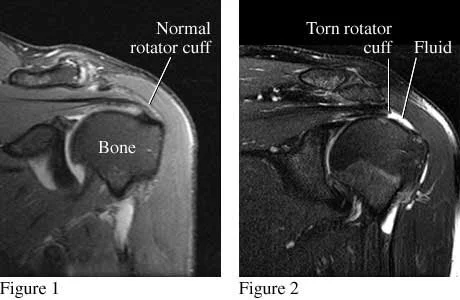

Most Adults Over 40 Show Rotator Cuff Abnormalities on MRI

The rotator cuff is a group of four muscles, the supraspinatus, the infraspinatus, the teres minor, and the suscapularis, and their tendons, which attach the muscle to the humurus. Rotator cuff tears are a common cause of shoulder pain. When folks present with significant weakness, severe pain, or persistent symptoms despite activity modification and physical therapy, we typically get an MRI.

We'd like to assume that what we find on MRI is the source of pain.

However, a new study out of Finland calls that assumption into question. The study looked at shoulders of adults in Finland aged 41-76. They found similar abnormalities no matter whether folks had symptoms or not. 96% of participants without symptoms had an abnormality on MRI in their rotator cuff, compared to 98% of folks with symptoms.

Dr. Neuman says: "This was a study of only Finnish adults, so these results may not be generalizable to everyone. Hard to know if what we find on the MRI is the source of the pain when 96% of people may have abnormalities at baseline. MRI of the shoulder might still be a useful tool for folks who are undergoing sugical consultation, as the MRI helps guide operation planning."